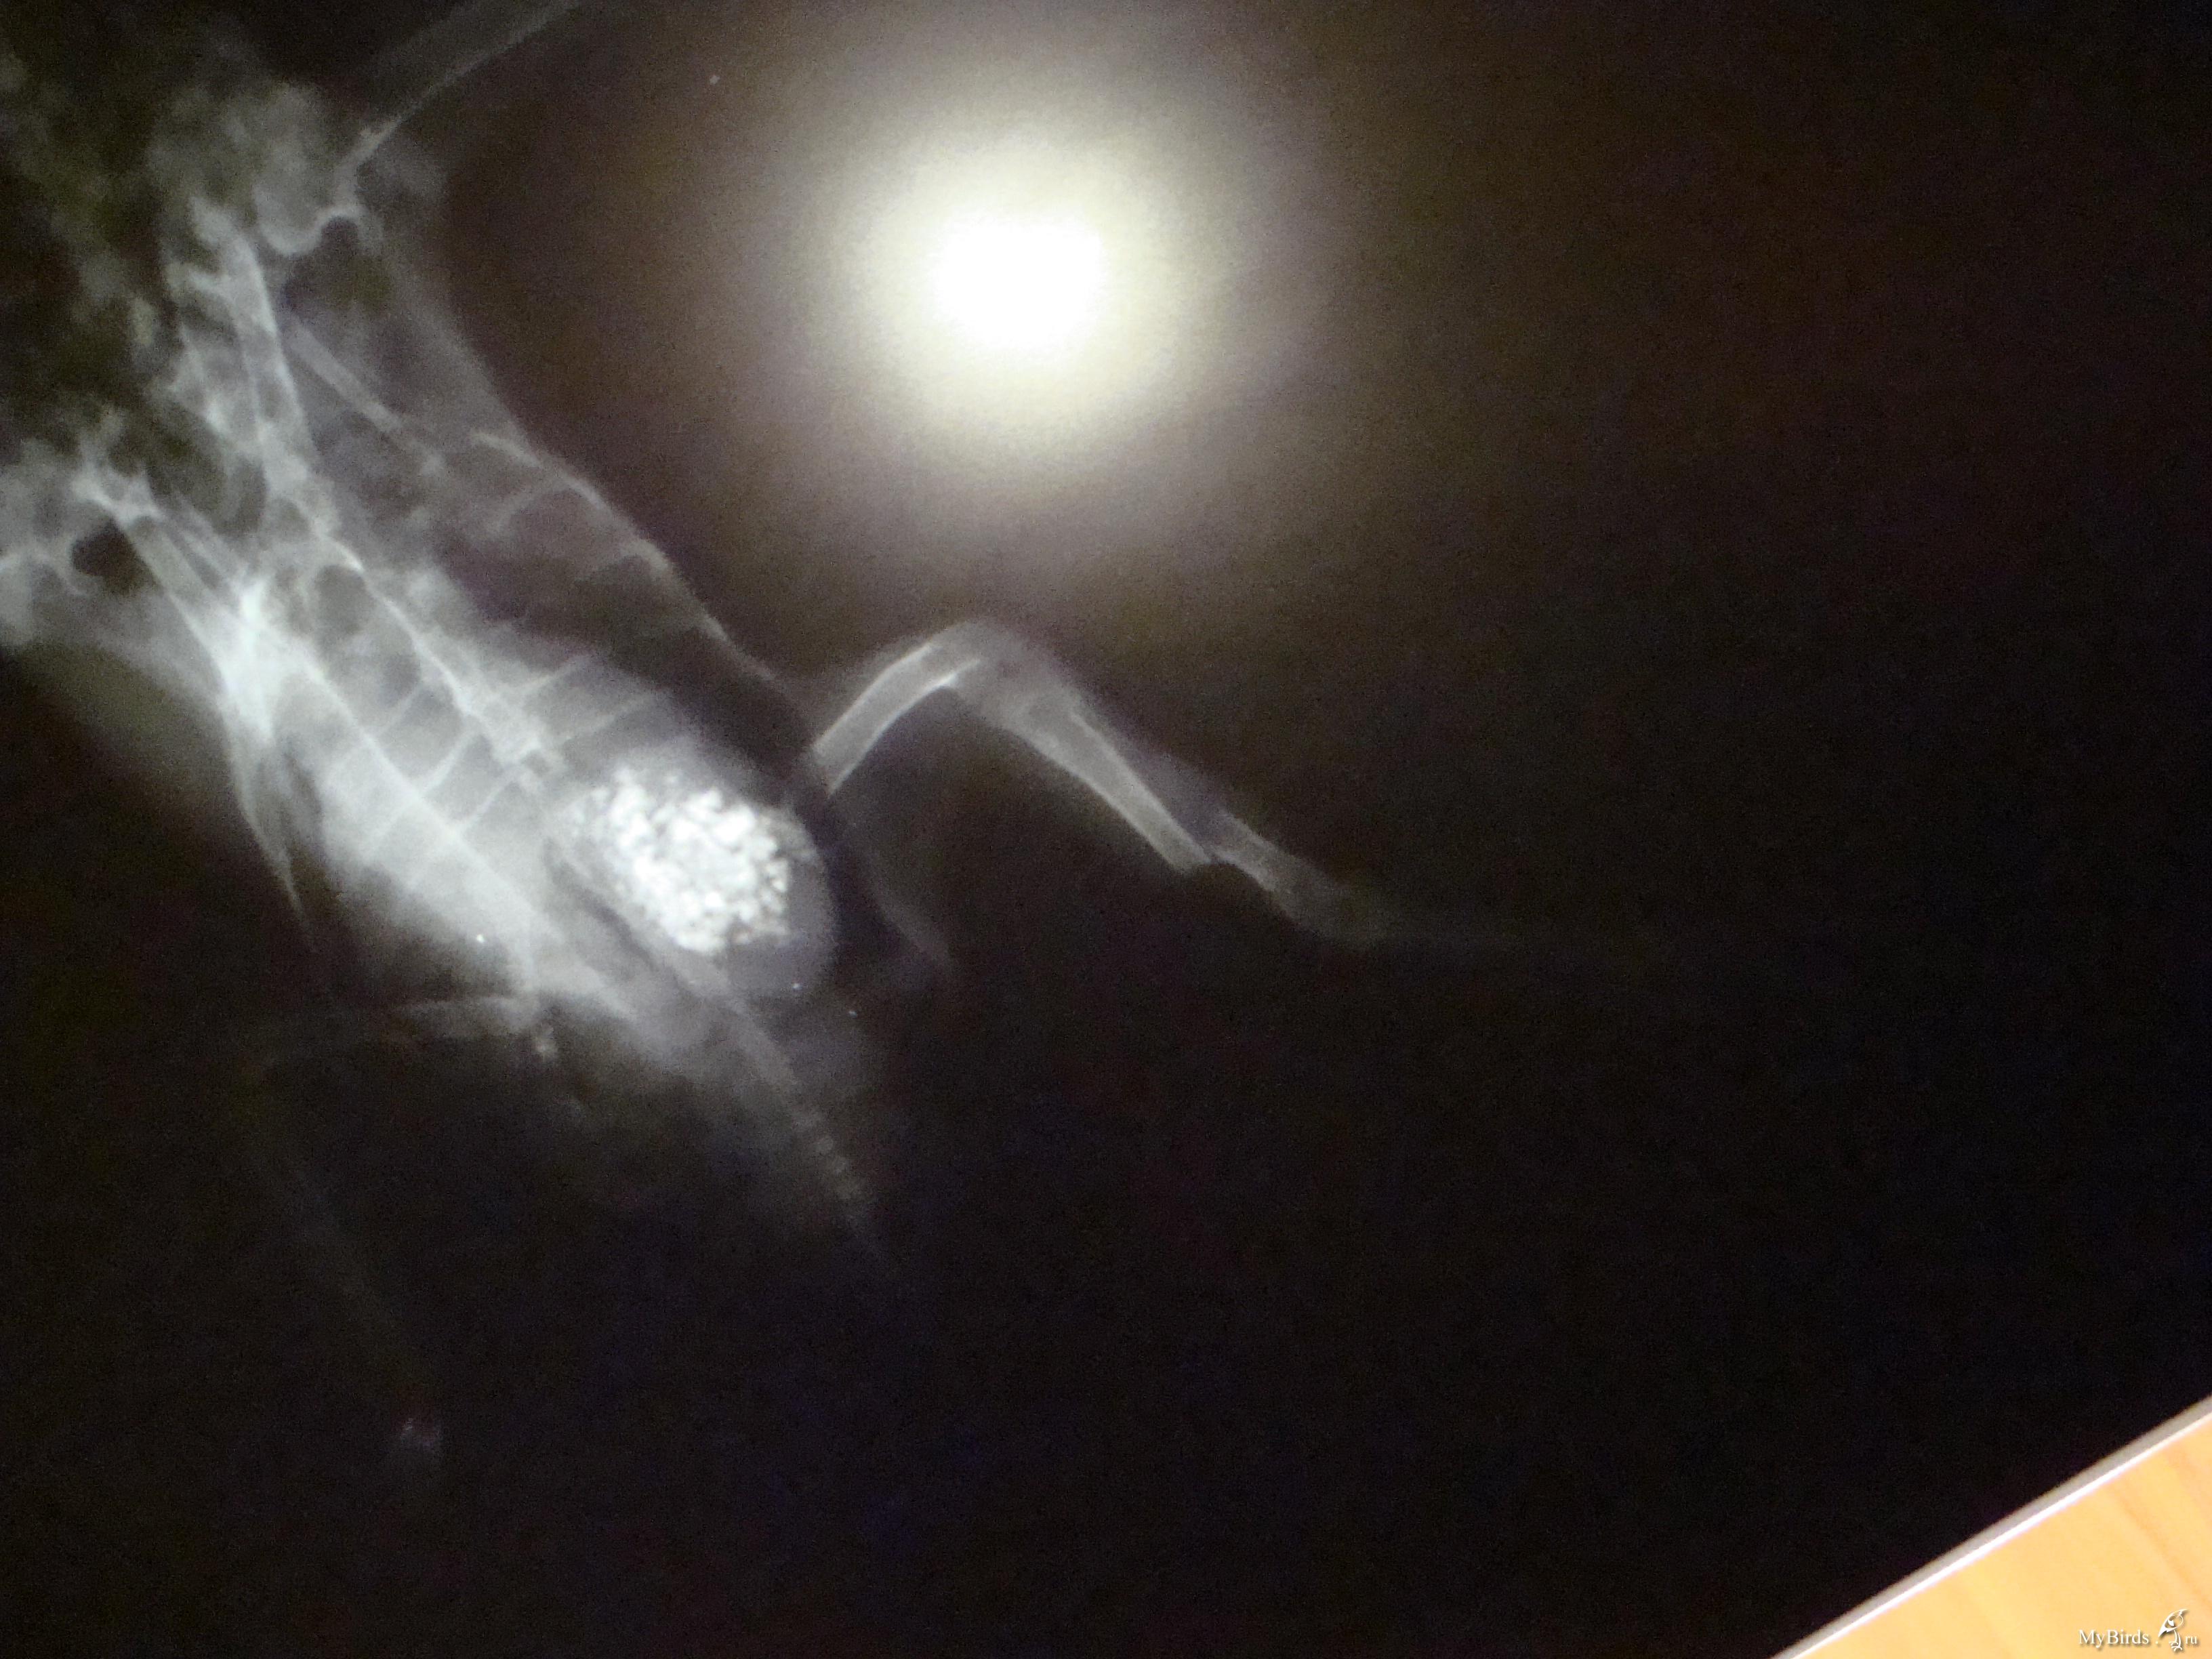

галина владимировна Опубликовано 11 сентября, 2009 Автор #118 Опубликовано 11 сентября, 2009 Это снимки Серого(тот,что с крылом).Хирург осмотрел крылья,проверил на рентгене и сказал,что перелома нет.У меня просьба.Пропишите пошагово ЧТО ДАВАТЬ,СКОЛЬКО И КАК ДОЛГО.Начиная с пробиотиков.И,если нужны витамины,то какие и тоже сколь.Схему лечения пропишите,пожалуйста,подробно(как для особо одаренных). Теперь Лапушка(тот,что с лапами).Для него такая же подробная нужна схема лечения.И чем протирать его гузку(попку).А то он лежит в своем помете часами. .Снимки,конечно ,оставляют желать лучшего.Но ,когда они были мокрыми,было видно хорошо.А высохли и изображение исчезло. У гули перелом обеих конечностей и перелом правого крыла.Хирург сказал,что крыло заживет само.А вот лапы..Переломы старые.Одна лапка сломана близко к суставу.Ее никто лечить не будет.А другую можно восстановить.Нужна операция. Операция стоит 6 тысяч.Помогите,пожалуйста, собрать средства!

Cheshirski Опубликовано 12 сентября, 2009 #120 Опубликовано 12 сентября, 2009 галина владимировна, поправил ваш пост с фотографиями - для удобства. Остальное - сейчас посмотрю-подумаю, и напишу. Снимки,конечно ,оставляют желать лучшего.Но ,когда они были мокрыми,было видно хорошо.А высохли и изображение исчезло.676983[/snapback] Маленький совет - просто вдруг в будущем пригодится. Снимки фотографировать лучше либо прямо на негаскопе (приспособление с подсветкой у врача в кабинете), либо на чем-то подобном дома (вроде светильника с лампами дневного света и молочным стеклом), а на худой конец - просто на окне, приклеив к стеклу скотчемза уголки, днем на фоне неба.Но ничего, и так все достаточно видно. Серенький. Да, переломов нет. Не видно и артроза - последствия сальмонеллы, к примеру - суставчики чистые (просто есть возможность сравнить - у меня есть снимок моего сальмонеллезника с артрозом). Тогда подвисание крыла - следствие ушиба или небольшого растяжения - они на снимке могут быть и не видны (сильные - видны в виде затемнения - притока крови к пострадавшему месту).Он не истощен? Пока кормите и добавьте в воду Ветом 1.1 - он есть? А в клюв ампульный препарат траумель, по такой схеме:Первый день приема - 2 капли в клюв каждые час.Второй день - 2 капли в клюв каждые 2 часаТретий день - 2 капли каждые 3 часа, и далее даете так, чтобы в день было не менее 3-4 приемов. Можно еще и крыло мазать траумелем (мазь), но если перьев много - то не стоит - оперение замаслится.И посмотрим за состоянием. Лапушка. Перелом крыла - да, такой сам срастется, если крыльями очень махать не будет. Смещение есть, но небольшое, на локтевой кости около запястного сустава. Даже летать сможет, скорее всего. И не исключено, что прилично летать.Лапы.Правая - да, трудный перелом. Думаю, стоит все же зафиксировать его, примерно вот так:Здесь черным обозначены кости, красным - место перелома, синим - плотный материал, вроде плотного картона, вырезан по месту, его два куска - с обоих сторон лапы - снаружи и изнутри, между лапой и телом. Конечно, подсогнуть надо будет, чтоб лапку облегал. А зеленым - места фиксации этой шины лейкопластырем. Другой вариант - выгнуть нечто подобное из жесткой (стальной) проволоки, и тоже закрепить на лапе пластырем. Возможно, что-то и удастся сделать, чтоб лапа более или менее правильно срослась. Левая. Тут попроще, кость сломана почти в середине. Что за операцйия предполагается? Остеосинтез - то есть, установка спицы? Попробуйте с врачом поговорить - не удастся ли просто совместить перелом и тоже наложить шину? Дело в том, что остеосинтез не всегда успешен у птиц - от многого зависит, и в любом случае, надо будет обеспечить неподвижность лапы, а со спицей это не всегда удается. Хотя, если у врача есть уверенность в результате - то можно попробовать. Про помет и т.д. При таких травмах не исключен и ушиб внутренних органов - той же печени. Плюс голодовка.Давайте ей траумель так же, как и Серенькому, и Ветом в воду тоже - по четверти чайной ложки на 100 мл поилки. Плюс карсил - по полтаблетки раз в день - это для печени, растолочь и давать в клюв разведенный водой до состояния кашицы.На кандиду картина не похожа, в крайнем случае - на нечто бактериальное. Пока не давайте, но имейте под рукой ципрофлоксацин 250 мг таблетки, наверняка еще остались. Если вдруг состояние кого-то из гуль будет хоть немного ухудшаться - давайте ципрофлоксацин в следующем разведении:1/2 таблетки развести в 4 мл воды, давать по 0,2 мл 2 раза в день в клюв. Если начнете его, то не прерывайте курс, давайте 10 дней. Если все же сделают остеосинтез - тогда надо будет поколоть другое лекарство, да и еще кое-что добавить, тогда и напишу. По поводу финансов - киньте в личку полный адрес, переводом сколько-то переправлю. ПС. В форуме, как правило, бываю каждый день. Так что не пропущу, единственно - не всегда удается отвечать оперативно.